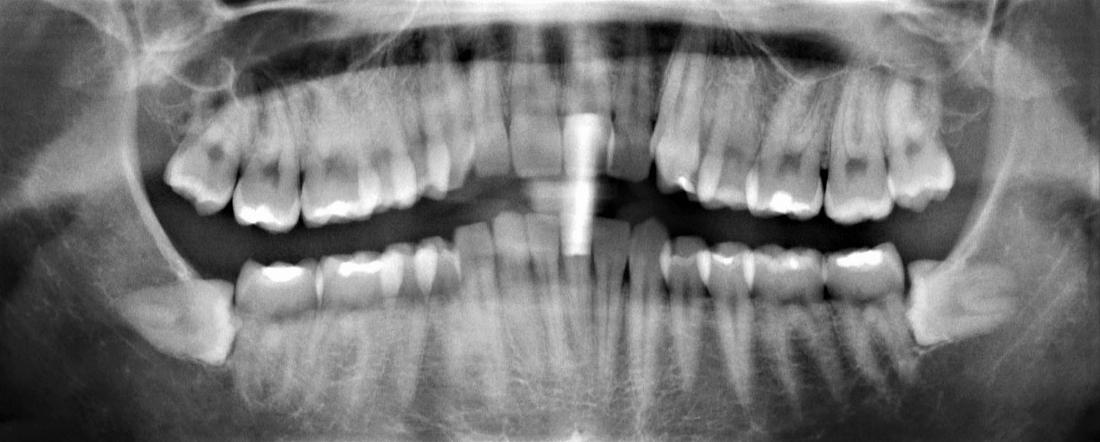

This patient underwent wisdom teeth removal. From discomfort to relief, these before-and-after images highlight how our skilled team ensures a smooth procedure, alleviating pain and safeguarding dental well-being.